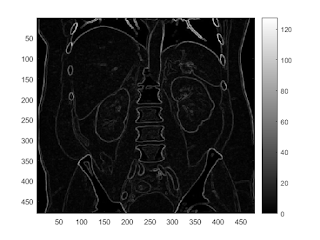

sobel edge filter

b = fspecial('sobel'); I2 = conv2(I,b,'same'); imagesc(I2); colorbar

imagesc(abs(I2)>200)